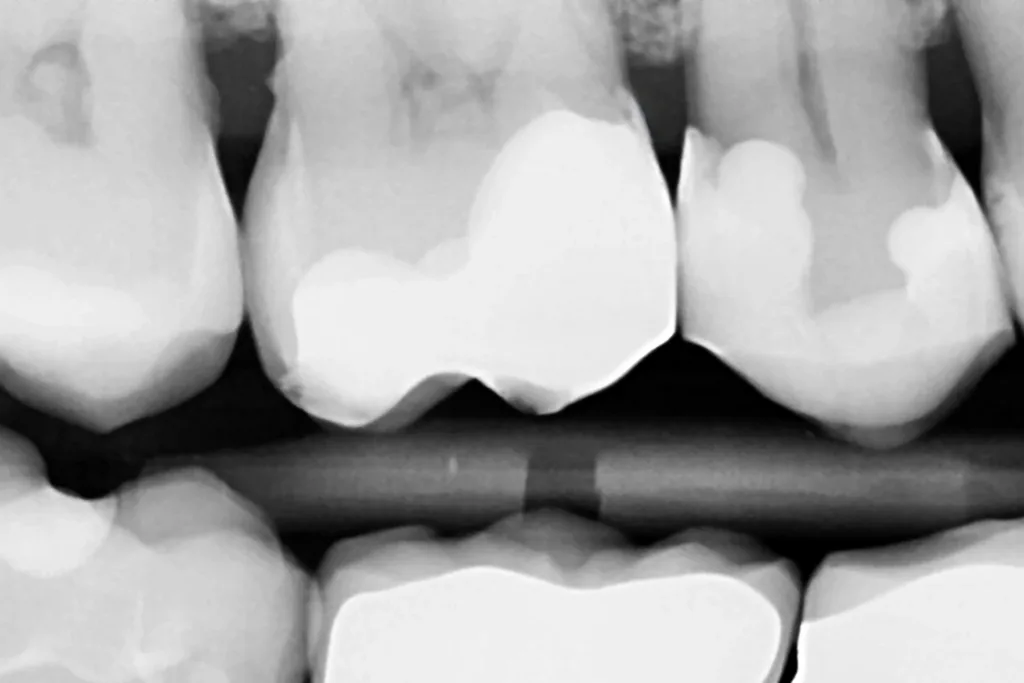

Die Versorgung des recht großen und tiefen Defektes erfolgte identisch zu den vorangegangenen Fällen mit einem Zwei-Schritt-Universaladhäsiv unter selektiver Schmelzätzung. GrandioSO Unlimited wurde hier erneut in der Farbe A1 angewendet, obwohl der Zahn tendenziell eine A2-Farbe aufwies. Die Verwendung der A1 war der zu diesem Zeitpunkt bereits verbrauchten A2-Farbe geschuldet. Da die A2 die am häufigsten verkaufte und damit auch verwendete Kompositfarbe darstellt, ist diese dementsprechend am schnellsten bei Intro-Kits aufgebraucht. Die in diesem Fall eingesetzte, etwas zu helle A1-Farbe passt sich dennoch erstaunlich gut der übrigen Zahnhartsubstanz an und ergab ein ansprechendes und völlig unauffälliges ästhetisches Erscheinungsbild, mit dem die Patientin auch sehr zufrieden war (Abb. 10). Dies war im vorliegenden Fall der Verwendung der deutlich dunkleren A3-Farbe vorzuziehen. Aufgrund der unklaren Befundungslage der mesialen Randleiste des Zahnes 17 wurde im Anschluss eine Bissflügel Röntgenaufnahme zur Kariesdiagnostik an Zahn 17 angefertigt. Hier zeigte sich keine Auffälligkeit in Form einer radiologisch erkennbaren Karies (Abb. 11). Die Patientin wurde zur sorgfältigen Zahnseidenanwendung instruiert, die Bedeutung einer fluoridhaltigen Zahnpasta betont und aufgrund der radiologisch feststellbaren Konkremente zur intensiveren Mundhygiene Aufklärung ein PZR-Termin vereinbart. Beeindruckend ist zudem die sehr hohe Röntgenopazität des GrandioSO Unlimited-Restaurationsmaterials im Zahn 16.